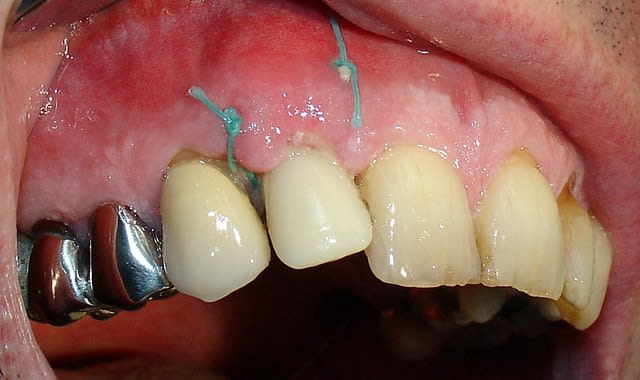

Quelques images de l'année dernière

A 8 jours  jfxlgy - Eugenol